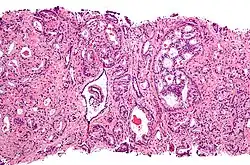

Для развития и целостного функционирования предстательная железа нуждается в андрогенах. Врождённая дисфункция андрогенового рецептора или 5-альфа-редуктазы у мужчин приводит либо к полному отсутствию, либо лишь к минимальному развитию предстательной железы. То же самое верно и для самцов других животных. Через неделю после кастрации предстательная железа самца крысы подвергается дегенерации из-за апоптоза эпителиальных клеток (после удаления семенников уровень андрогенов недостаточен для поддержания целостности простаты). Андрогены также относятся к факторам, стимулирующим развитие рака предстательной железы. Изучение евнухоидных индивидуумов показало, что у них простата остаётся маленькой и не подвергается гипертрофии или злокачественному перерождению. Более того, в животных моделях канцерогенеза в предстательной железе необходимо наличие семенников или экзогенных андрогенов для поддержания развития опухоли. У трансгенных мышей с повышенной экспрессией AR в простате клетки эпителия простаты обновляются гораздо быстрее, чем в норме, и простатическая интраэпителиальная неоплазия (злокачественное новообразование) у таких мышей появляется значительно раньше. Хотя необходимость андрогенов для развития рака простаты не вызывает сомнений, сложно установить связь между относительным уровнем андрогенов в крови и риском развития рака простаты. Для объяснения различий в частоте возникновения и степени выраженности рака простаты были предложены расовые различия в уровне циркулирующих в крови андрогенов. Впрочем, данные по связи между уровнем андрогенов в крови и риском развития рака предстательной железы весьма противоречивы, и окончательного решения по этому вопросу нет. Возможно, противоречивость данных объясняется варьирующей активностью андрогеновых рецепторов, которая может играть исключительно важную роль в развитии рака простаты[10].